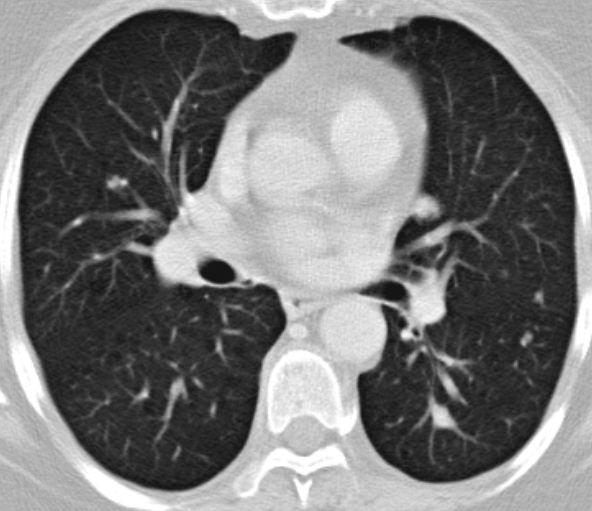

| Metastasierung | Lungenmetastasen und Lokalrezidiv 1 Jahr nach Leiomyosarkom der rechten Beckenwand.

![]() | ||